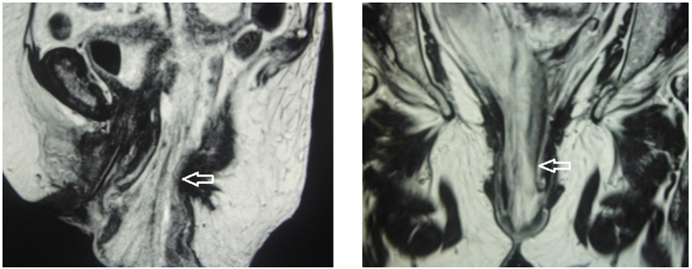

Con lo anterior, se planteó el diagnóstico de evisceración intestinal transvaginal incarcerada con perforación y obstrucción intestinal en resolución. Se inició nutrición parenteral total cinco días después y se solicitó una resonancia magnética abdominopélvica que reveló introito vaginal ampliado de 5 cm de diámetro anteroposterior, el cual estaba ocupado en su interior por asas intestinales y mesenterio protruido (Figura 3).

Figura 3. Resonancia magnética de la pelvis, donde se observa el introito vaginal ampliado, de 5 cm de diámetro, por donde protruyen las asas intestinales y el mesenterio (flechas). Fuente: original de los autores.